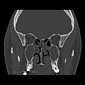

Coronal non-contrast

• Title: Headache and rhinorrhoea

• Diagnosis Title: Sinusitis